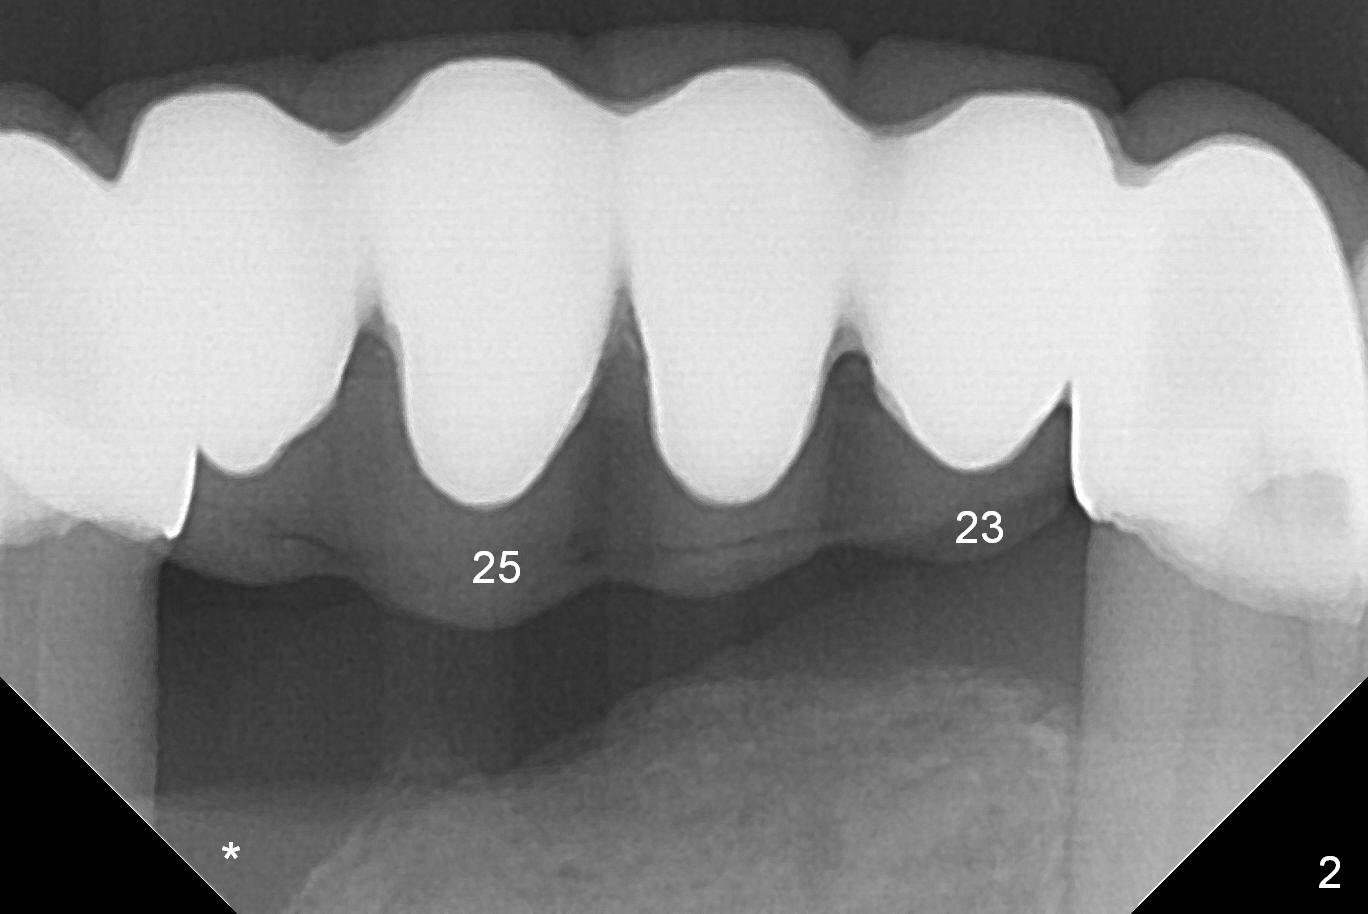

A 57-year-old woman has a 20-year-old loose FPD (fixed partial denture, Fig.1-3). Upon Alginate impression for stent, the 6-unit FPD was dislodged with the exfoliated abutment at #27. After removal of calculus from the root of #27, the FPD was placed in situ and temporarily cemented to #22 abutment. When the patient returns, remove the FPD, treat the socket of #27 with Clindamycin, place implants at #23, 25 and 27 and fabricate a 6-unit provisional FPD. At definitive stage of restoration, fabricate a 4-unit FPD at #24-26 and a single unit at #27. Since bone loss is more severe mesiobuccally at #27 (Fig.1), place an implant as lingual as possible, but slightly more mesially. If the defect is so severe that the implant (green) has to be placed deep, the abutment margin with the longest cuff (5 mm, pink) is less likely to contact the distal crest (*). Crown margin (i.e., abutment margin of an implant) should be 2 mm more coronal to the crest normally. The condition that does not meet the requirement is called violation of biologic width, associated with periodontitis or periimplantitis.

For the same token (severe bone loss at the mesial aspect of the site of #27), the site of #26 is not a good candidate one for implantation (Fig.2 *). The site of #25 is most likely a better one. The site of #23 should be the most favorite one among #23-26, since the edentulous site next to the dentate one is less likely resorbed after extracted. For a FPD, abutments should be far away from each other. No matter what, prepare 1-piece implants (as small as 2.5 and 2.0 mm ones) and surgical handpiece (why?). Take preop photos to show recessive gingiva at #27.